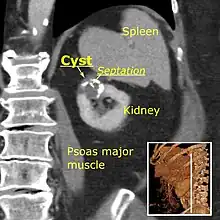

A very small (8 mm) simple renal cyst. Bosniak II cyst at the lower pole of right kidney with septations within.

Bosniak II cyst at the lower pole of right kidney with septations within.